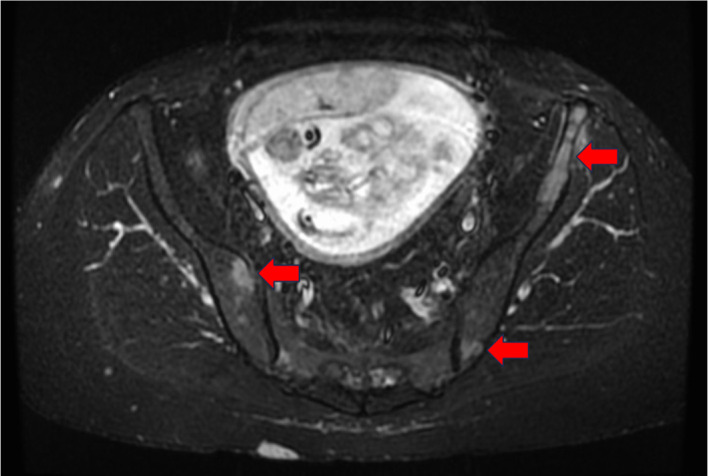

Case: A 41-year-old pregnant woman was admitted to our hospital because low back pain compromised her ability to stand. She was diagnosed with breast cancer-associated multiple bone metastases. Our unit was consulted for rehabilitation therapy, for which we formed a BMCB. The treatment was integrated and performed according to the recommendations of the BMCB. The patient underwent a cesarean section to initiate primary tumor treatment. After evaluating the risk of SREs, we provided her with rehabilitation therapy. Wearing a plastic molded thoracolumbosacral orthosis, she was able to walk with a pick-up walker. The patient continued outpatient chemotherapy and cared for her infant without experiencing any significant adverse events.

Abstract Image